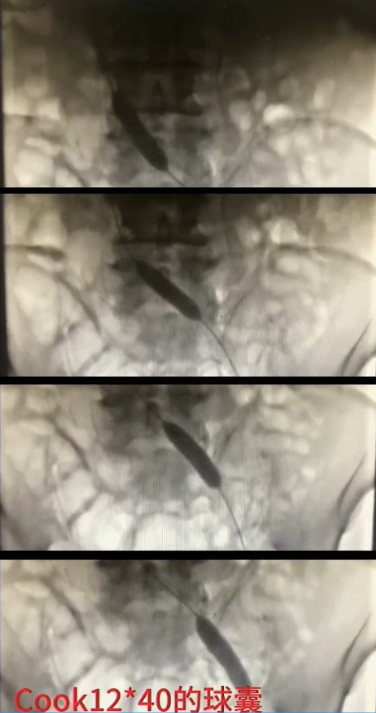

手术过程(五):复查造影见髂总静脉处仍狭窄,与家属沟通后,同意置入支架。引入髂静脉支架,定位准确后,谨慎释放,12 mm×40 mm球囊扩张髂静脉支架。

手术过程(六):造影见髂静脉血流通畅,支架形态满意,血流速度可,侧支循环消失。遂拔除鞘管,加压包扎,手术完成。